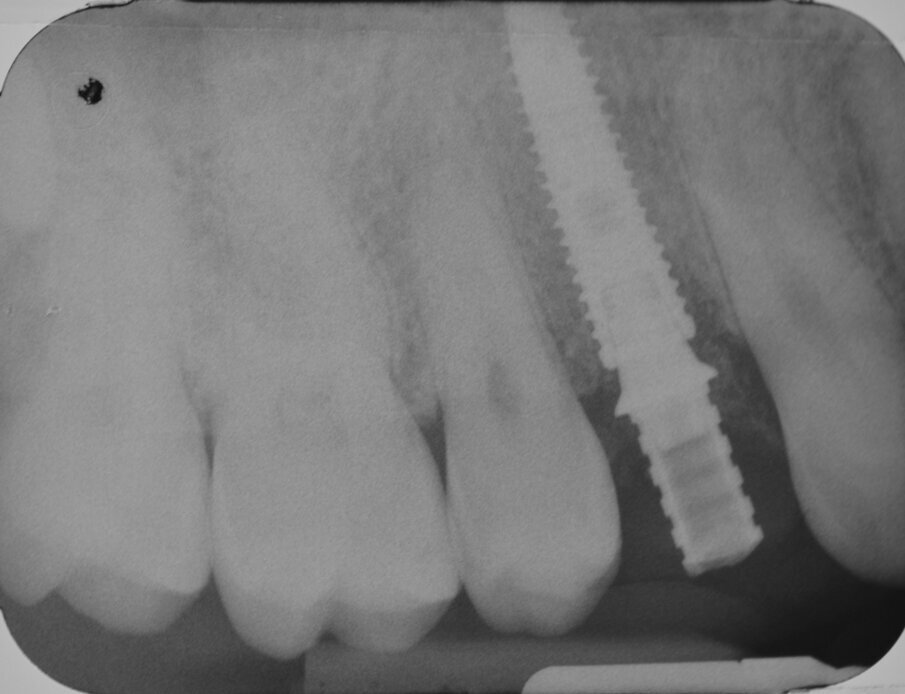

All’esame obiettivo viene si evidenzia una frattura verticale a carico dell’elemento in questione (Figg. 1, 2) che pone indicazione assoluta all’estrazione dentaria; per evitare di aggravare l’inevitabile contrazione della cresta ossea alveolare, si decide di eseguire l’estrazione dell’elemento fratturato senza sollevare alcun lembo. Viene effettuato un esame radiografico endorale allo scopo di visualizzare la morfologia della radice dentaria e i suoi rapporti con le strutture viciniori. (Fig. 3)

Dopo aver protetto il sito chirurgico mediante un frammento di diga sterile (Fig. 15) una corona provvisoria in resina viene adeguatamente ribasata sul temporary abutment avvitato all’impianto, avendo cura di evitare qualsiasi tipo di contatto sia in occlusione centrica che durante i movimenti di lateralità e protrusione (Figg. 16, 17). Prima di dimettere il paziente con la corona provvisoria in situ, viene eseguito un esame radiografico endorale di controllo: trattandosi di un impianto “bone level” è consigliabile inserirne la piattaforma implantare circa 0,5 - 1 mm apicalmente alla cresta ossea marginale (Fig. 18).

Dopo aver opportunamente preparato un abutment definitivo che sia idoneo per altezza e forma del segmento transmucoso, si procede alla cementazione di una corona protesica definitiva in zirconia stratificata. Le immagini del follow-up a 12 mesi (Figg. 23-25) e il contestuale controllo radiografico endorale (Fig. 26) indicano un’ottima risposta dei peri-implantari tessuti duri e molli.

Fig. 3 - Esame radiografico endorale preoperatorio.

Fig. 18 - Esame radiografico endorale di controllo.

Fig. 26 - Esame radiografico endorale di controllo.